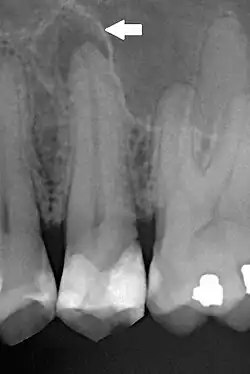

| Periapical dental radiograph showing chronic periapical periodontitis on the root of the left maxillary second premolar. Note large restoration present in the tooth, which will have undergone pulpal necrosis at some point before the development of this lesion. | |

Periapical periodontitis or apical periodontitis[9] (AP) is an acute or chronic inflammatory lesion around the apex of a tooth root, most commonly caused by bacterial invasion of the pulp of the tooth.[10] It is a likely outcome of untreated dental caries (tooth decay), and in such cases it can be considered a sequela in the natural history of tooth decay, irreversible pulpitis and pulpal necrosis. Other causes can include occlusal trauma due to 'high spots' after restoration work, extrusion from the tooth of root filling material, or bacterial invasion and infection from the gums. Periapical periodontitis may develop into a periapical abscess, where a collection of pus forms at the end of the root, the consequence of spread of infection from the tooth pulp (odontogenic infection), or into a periapical cyst, where an epithelial lined, fluid-filled structure forms.

The radiographic features of periapical inflammatory lesions vary depending on the time course of the lesion. Because very early lesions may not show any radiographic changes, diagnosis of these lesions relies solely on the clinical symptoms. More chronic lesions may show lytic (radiolucent) or sclerotic (radiopaque) changes, or both.